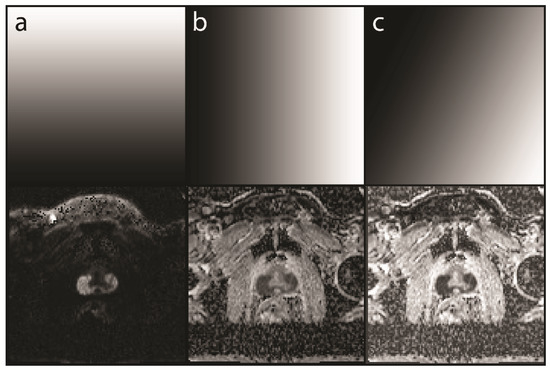

Figure 3. Examples of different readouts from a mcDI dataset created from a high b-value DWI (hbDWI), the ADC, and an intensity map. The selected map is shown in the top row and the resulting mcDI in the bottom row. (a) A readout with a strict vertical gradient yields the original DWI. The resulting image contains no ADC information; (b) In contrast to (a), a strict horizontal gradient yields the original ADC image; (c) A tilted gradient yields the mcDI containing both the DWI and ADC information with an even lower signal in the large tumor in the peripheral zone of the prostate and a lighter background.

The 2D histograms of these 70 patients (training dataset) were analyzed, and the PCa and normal prostate tissue areas were defined. The size, shape, and location of these areas were used to generate rules for the creation of a so-called intensity map. These rules were translated into gradients that were plotted onto the intensity map. Those rules are explained in detail in the Results. Finally, for each DWI-ADC image pair, a mcDI was generated by plotting the intensity map values back onto the initial voxel locations. For example, tumor voxel A (0.3, 0.2) corresponds to an intensity of 70% gray on the intensity map. Therefore, the voxel in the mcDI will be represented by this dark color. This whole algorithm is visualized in Figure 2. Examples of different readouts are presented in Figure 3.

In routine clinical practice, a combination of a low and a high b-value is seldom read in isolation. It is standard to calculate an ADC, and in many cases, a higher b-value is calculated to enhance the sensitivity for tumor detection [13,14]. These calculations are, however, purely mathematical and highly standardized; therefore, no knowledge of the underlying tissue is used to enhance the images, especially for a specific study. The present study produced two findings that are commonly known to radiologists but are not yet implemented in image creation. First, tumor conspicuity increases with the increasing signal in hbDWI and decreasing intensity in ADC. We used this characteristic by tilting the axis of the grayscale gradient to combine the information of both images (Figure 3). Second, most of the background has a low signal in the hbDWI, while there are no tumor voxels below a certain threshold. This no-tumor zone was used to reduce the background without losing contrast in the tumor (Figure 4).